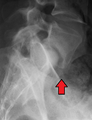

X-ray picture of a grade 1 isthmic spondylolisthesis at L4-5

X-ray picture of a grade 1 isthmic spondylolisthesis at L4-5 MRI of L5-S1 spondylolisthesis

MRI of L5-S1 spondylolisthesis- X-ray of a grade 4 spondylolisthesis at L5-S1 with spinal misalignment indicated